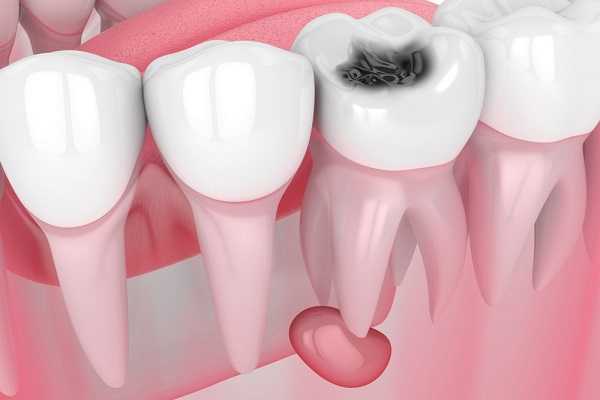

Радикулярная киста - это полостное образование в области верхушки корня зуба, выстланное изнутри эпителиальной тканью и заполненное кистозной жидкостью. Является исходом хронического периапикального воспаления. Пациент с радикулярной кистой может не предъявлять никаких явных жалоб, они возникают при нагноении содержимого или прорастании кисты в гайморову пазуху. Длительное существование кисты приводит к деформации костной ткани и повышению риска перелома челюсти. Для диагностики используются данные объективного осмотра, дентальной рентгенографии, электроодонтометрии и пункции с последующим цитологическим исследованием. Лечение радикулярной кисты производится хирургическим путем.

Патанатомия

Корневая киста формируется из эпителиальных клеток под влиянием воспалительного процесса в тканях периодонта. Она имеет тонкие фиброзные стенки, изнутри выстлана многослойным плоским эпителием и заполнена желтой прозрачной жидкостью с кристаллами холестерина. Образование формируется либо непосредственно на верхушке корня зуба - такая киста называется апикальной, либо прилежит к латеральной поверхности корня и тогда классифицируется как латеральная периодонтальная киста.